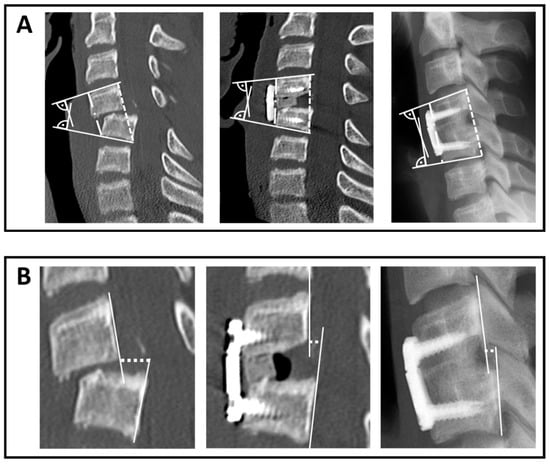

3.5.1. Reduction and Loss of Reduction in Terms of mEA and bEA

3.5.2. Anterior Translation